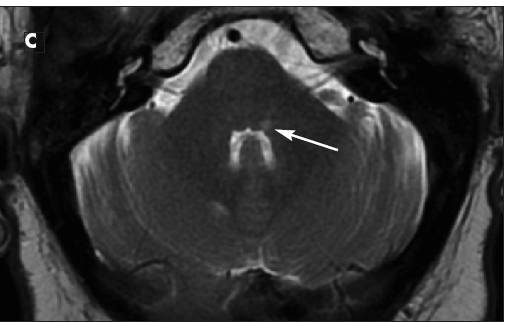

A CT scan of the brain revealed 3 to 4 cm of vasogenic edema in the right posteroinferior parietal-occipital area. Axial T1-weighted (B) and T2-weighted (C) images showed an enhancing lesion in the medial longitudinal fasciculus. A full-body CT scan was negative for malignancy. Lumbar puncture revealed oligoclonal bands in the cerebrospinal fluid; a workup for Lyme disease, Cryptococcus infection, fungal infection, HIV and other viral infections, and bacterial (including acid-fast bacilli) infection yielded negative results.

These results confirmed the suspected diagnosis of tumefactive (atypical) multiple sclerosis (MS). This rare form of demyelinating disease is characterized by atypical MRI findings of mass-like demyelination.1